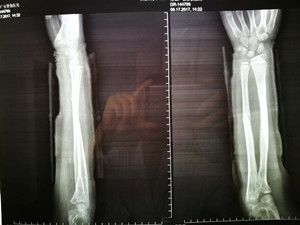

(整复前拍片)

看到女儿弯曲畸形的前臂,心疼不已的爸爸妈妈连忙抱起小女孩奔入附近的东港某骨科医院。X线片显示:左尺、桡骨骨折,骨折严重移位。这时,妈妈首先想到的广安医院正骨科虞杰主任。之前,她曾在广安医院正骨科就诊,对正骨科医护人员的服务态度、服务质量及医疗技术非常信任。

(整复后拍片)